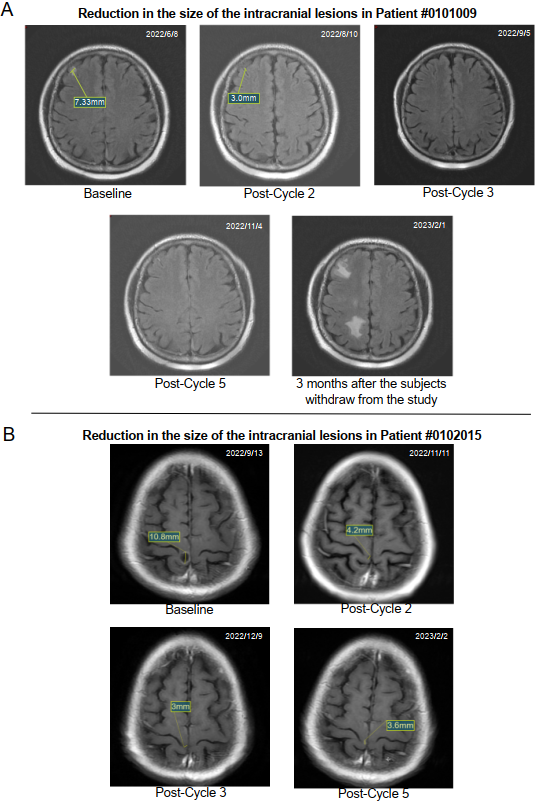

Figure 2 shows the magnetic resonance imaging scans of the brain lesions for two typical patients. In these patients, the median time to respond was 1.8 months (range 1.7-1.8 months), and the median iPFS was 8.0 months (95% CI 4.7-16.0 months).

Figure 1 presents the DepORs in the 17 patients with BMs. The iORR was 41% (7/17) (95% CI 18.4% to 67.1%), the iDCR was 76% (13/17) (95% CI 50.1% to 93.2%), and the medium iDepOR was 34.4% (range 0.4%-100%).